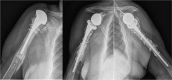

The reported rate of complications of reverse shoulder arthroplasty (RSA) seems to be higher than the complication rate of anatomical total shoulder arthroplasty.The reported overall complication rate of primary RSA is approximately 15%; when RSA is used in the revision setting, the complication rate may approach 40%.The most common complications of RSA include instability, infection, notching, loosening, nerve injury, acromial and scapular spine fractures, intra-operative fractures and component disengagement.Careful attention to implant design and surgical technique, including implantation of components in the correct version and height, selection of the best glenosphere-humeral bearing match, avoidance of impingement, and adequate management of the soft tissues will hopefully translate in a decreasing number of complications in the future. Cite this article: Barco R, Savvidou OD, Sperling JW, Sanchez-Sotelo J, Cofield RH. Complications in reverse shoulder arthroplasty. EFORT Open Rev 2016;1:72-80. DOI: 10.1302/2058-5241.1.160003.